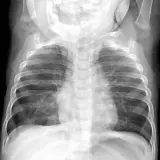

Over 2,100 interactive radiology cases, curated by radiologists for your level of training. Scroll, window, and view cases full screen — just like on PACS. Click linked findings in each writeup to jump straight to them on the image. Cases include sample reports, a focused discussion section, original illustrations, and videos.

Our site includes 3 main courses: Call Preparation, Introduction to Radiology, and Neuro Fellowship.

Call Preparation — our comprehensive curriculum for junior residents preparing for call covering both classic and atypical presentations. Use the call simulator to practice a real call shift — shuffle cases, enter your own preliminary report, and receive constructive AI feedback.

Intro to Radiology — a course coming later this year designed specifically for beginners. Terms are defined inline, lessons include introductory videos, and cases include guided video reviews by a radiologist who steps you through every finding. Lessons also include high-yield multiple choice questions that reinforce what you've learned and prepare you for boards.

Casos totalmente interativos com as ferramentas que você espera em um PACS — rolagem, ajuste de janela, zoom, movimentação, medidas, ROIs e modo de tela cheia.

Anotações detalhadas destacam os achados principais diretamente nos casos. Clique nos achados vinculados nas descrições dos casos para ir ao local exato no exame.